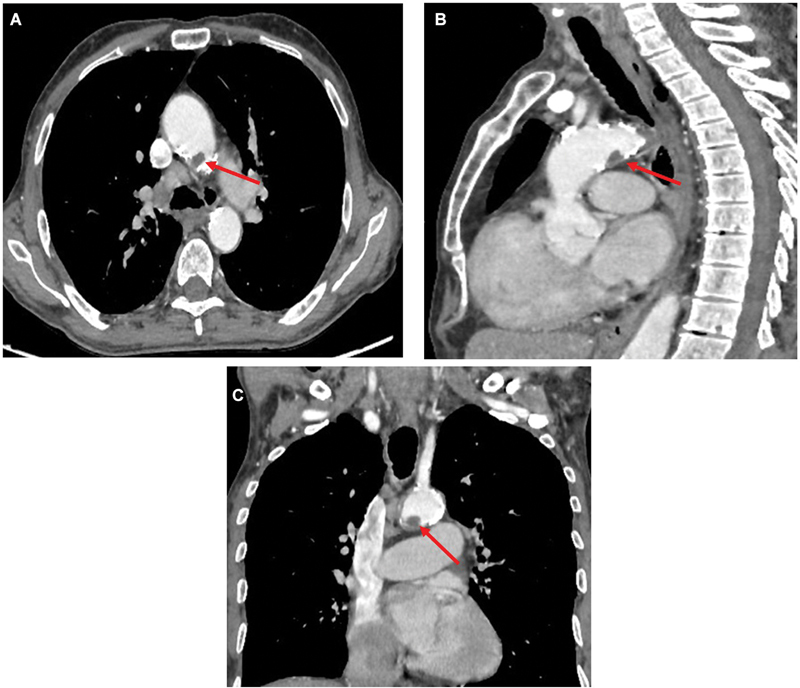

主动脉浮栓是一种罕见的危及生命的疾病。大多数主动脉血栓病例都是在发生栓塞事件后才被诊断出来的;然而,在极少数情况下,我们可能会在常规检查中偶然诊断出这种疾病,就像我们的病例一样。

Aortic floating thrombus is a rare, life-threatening disease. Most cases of aortic thrombus are diagnosed after embolic events; however, on rare occasion we may diagnose this condition incidentally during routine examinations as in our case.